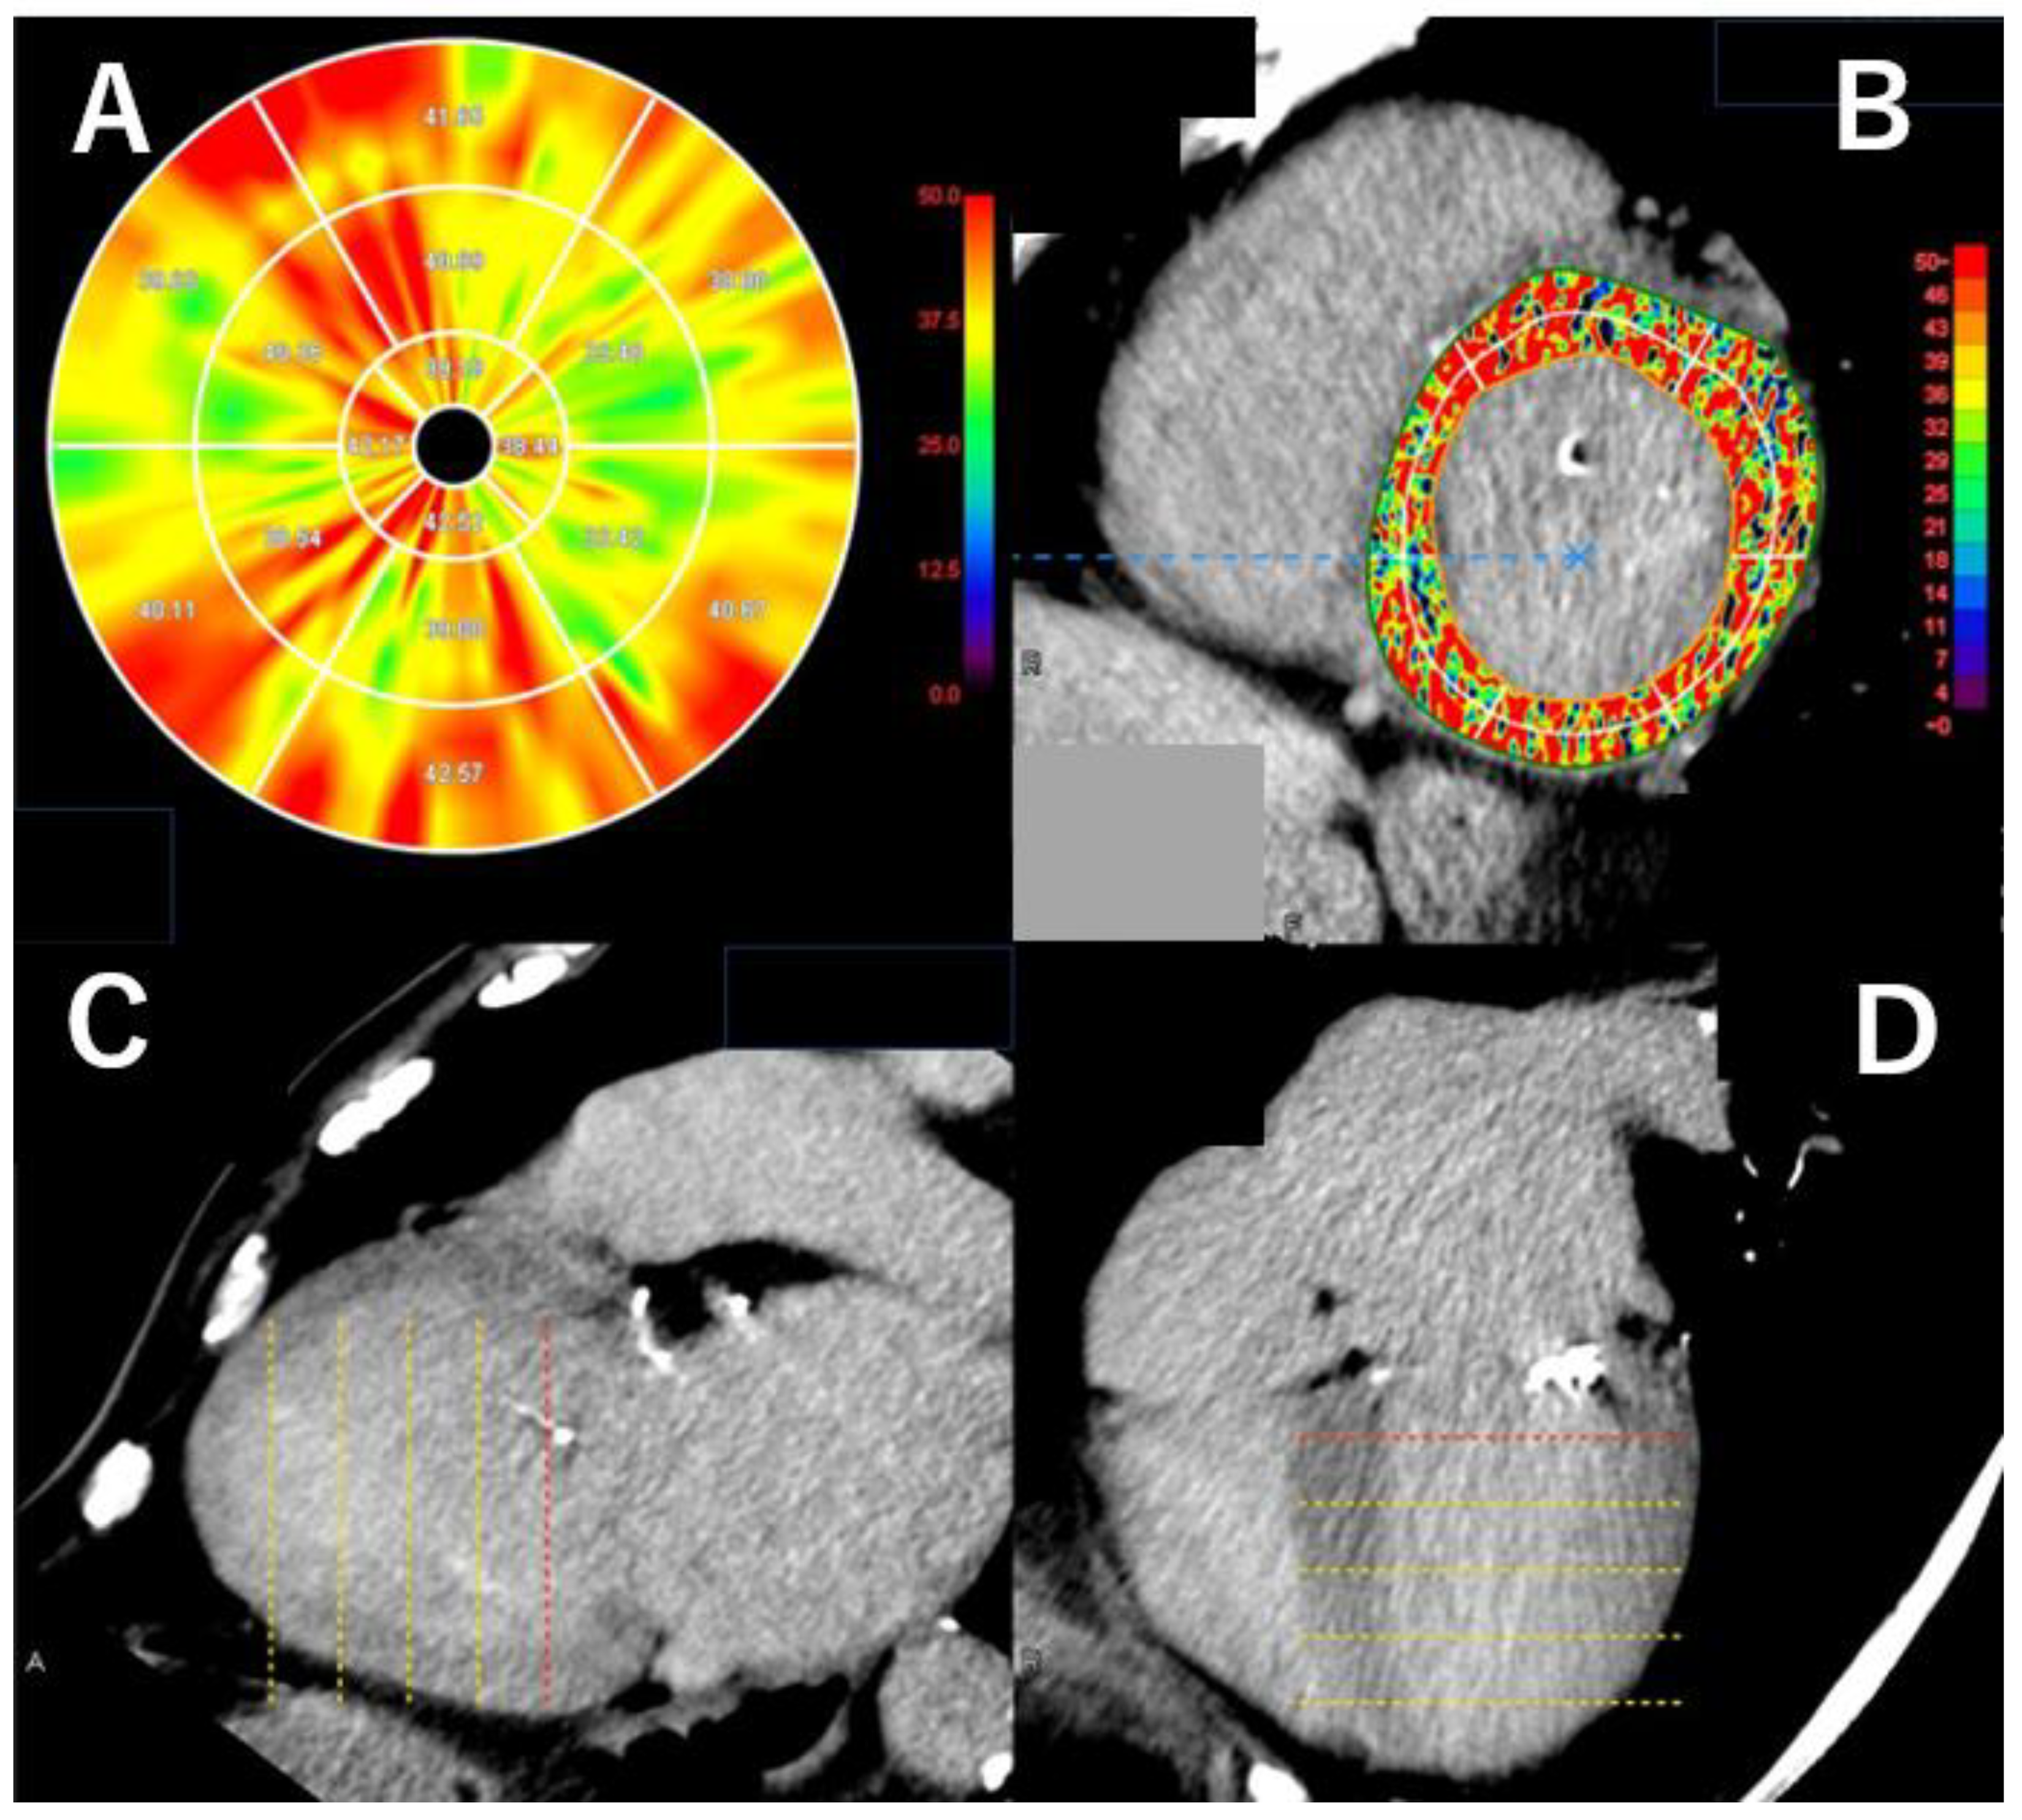

3.5. The Analysis of Myocardial Damage on Computed Tomography

3.6. Myocardial Strain Analysis on Computed Tomography

- Andreini, D.; Conte, E.; Mushtaq, S.; Melotti, E.; Gigante, C.; Mancini, M.E.; Guglielmo, M.; Lo Russo, G.; Baggiano, A.; Annoni, A.; et al. Comprehensive Evaluation of Left Ventricle Dysfunction by a New Computed Tomography Scanner: The E-PLURIBUS Study. J. Am. Coll. Cardiol. Imaging 2023, 16, 175–188. [Google Scholar] [CrossRef]

- Aoki, S.; Takaoka, H.; Ota, J.; Kanaeda, T.; Sakai, T.; Matsumoto, K.; Noguchi, Y.; Nishikawa, Y.; Yashima, S.; Suzuki, K.; et al. Strong Diagnostic Performance of Single Energy 256-row Multidetector Computed Tomography with Deep Learning Image Reconstruction in the Assessment of Myocardial Fibrosis. Intern. Med. 2024, 63, 2499–2507. [Google Scholar] [CrossRef]

- Bernhard, B.; Schütze, J.; Leib, Z.L.; Spano, G.; Berto, M.B.; Bakula, A.; Tomii, D.; Shiri, I.; Brugger, N.; De Marchi, S.; et al. Myocardial analysis from routine 4D cardiac-CT to predict reverse remodeling and clinical outcomes after transcatheter aortic valve implantation. Eur. J. Radiol. 2024, 175, 111425. [Google Scholar] [CrossRef]